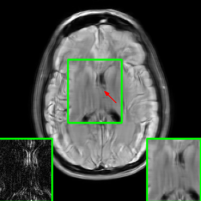

Here, we employ the fastMRI+ dataset to assess our approach’s image reconstruction capability. For the training phase, we employ the original fastMRI brain dataset, which excludes lesion cases, as the basis for training all methods. During the testing phase, however, we utilize the lesion dataset. Table II shows the results, where our method reports the highest PSNR and SSIM values compared to other baselines. It is important to highlight that, unlike the cases of additive k-space noise and training/testing sampling protocol and undersampling rate disparities, the improvements observed from utilizing our method with unseen lesions are somewhat marginal as seen from the average PSNR and SSIM results (at least 1.2 dB PSNR improvement when compared to the 2nd best results). Additionally, visualizations are provided Figure 13 where we highlight the nonspecific white matter lesion area. As observed, both visually and in terms of PSNR values, our approach reports improved results when compared to the other baselines.

In Figure 14, we report results (PSNR in the y-axis) of our method (labeled as ‘Ours’ and ‘Ours DDIM’) and baselines using measurements with unseen lesions combined with worst-case additive noise (generated by the PGD method) with budget indicated in the x-axis. We include these results to evaluate our method and baselines using a scenario that combines multiple sources of instabilities. As observed, our methods report the best results.